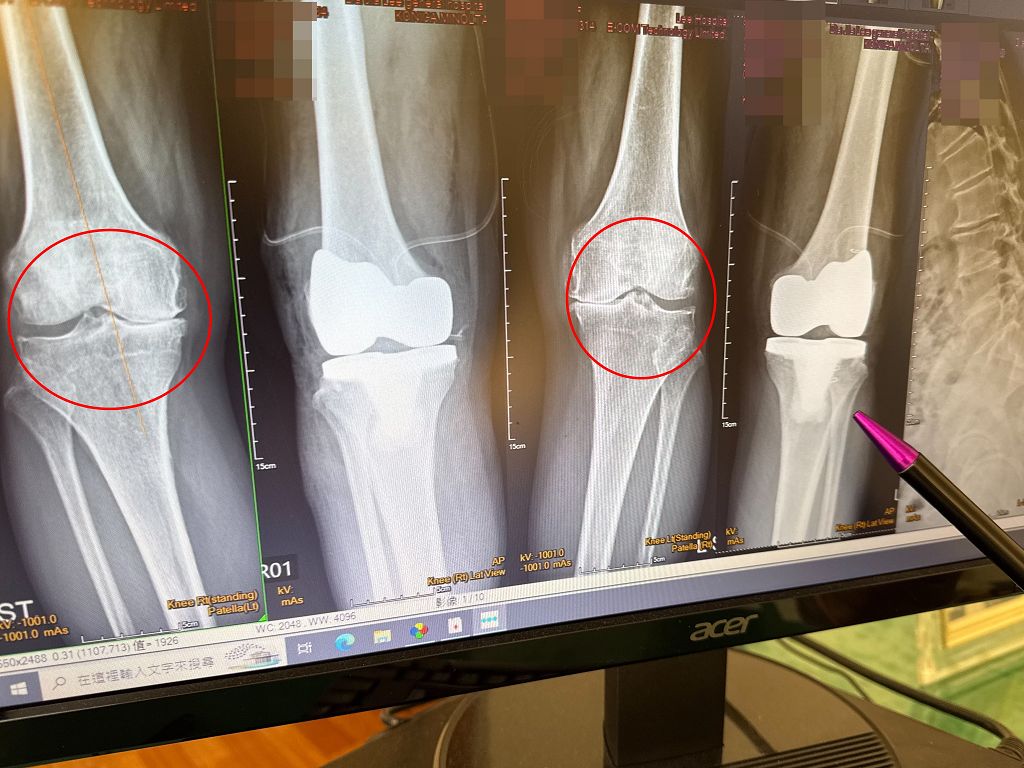

大甲李綜合醫院副院長、骨科主治醫師王芳英表示,患者是第四期的退化性關節炎,雙腳內翻變成10度,外觀看起來呈現O型腿,腳無法伸直,另外脊椎第2到第5節滑脫長骨刺,背部往前傾。門診時,患者非常困擾,詢問「我到底要先治療雙膝還是脊椎」,他分析後建議先置換人工膝關節。

王芳英進一步說明,患者雙膝變形嚴重無法站直,如果沒有先開刀治療,背部會持續往前傾,同時向患者建議,一次進行雙腳的膝關節置換,避免完成單腳人工膝關節置換後造成長短腳,在身體重心不穩走路下,讓脊椎滑脫的症狀更加嚴重。患者在置換雙膝後,隔天便能下床正常走路。